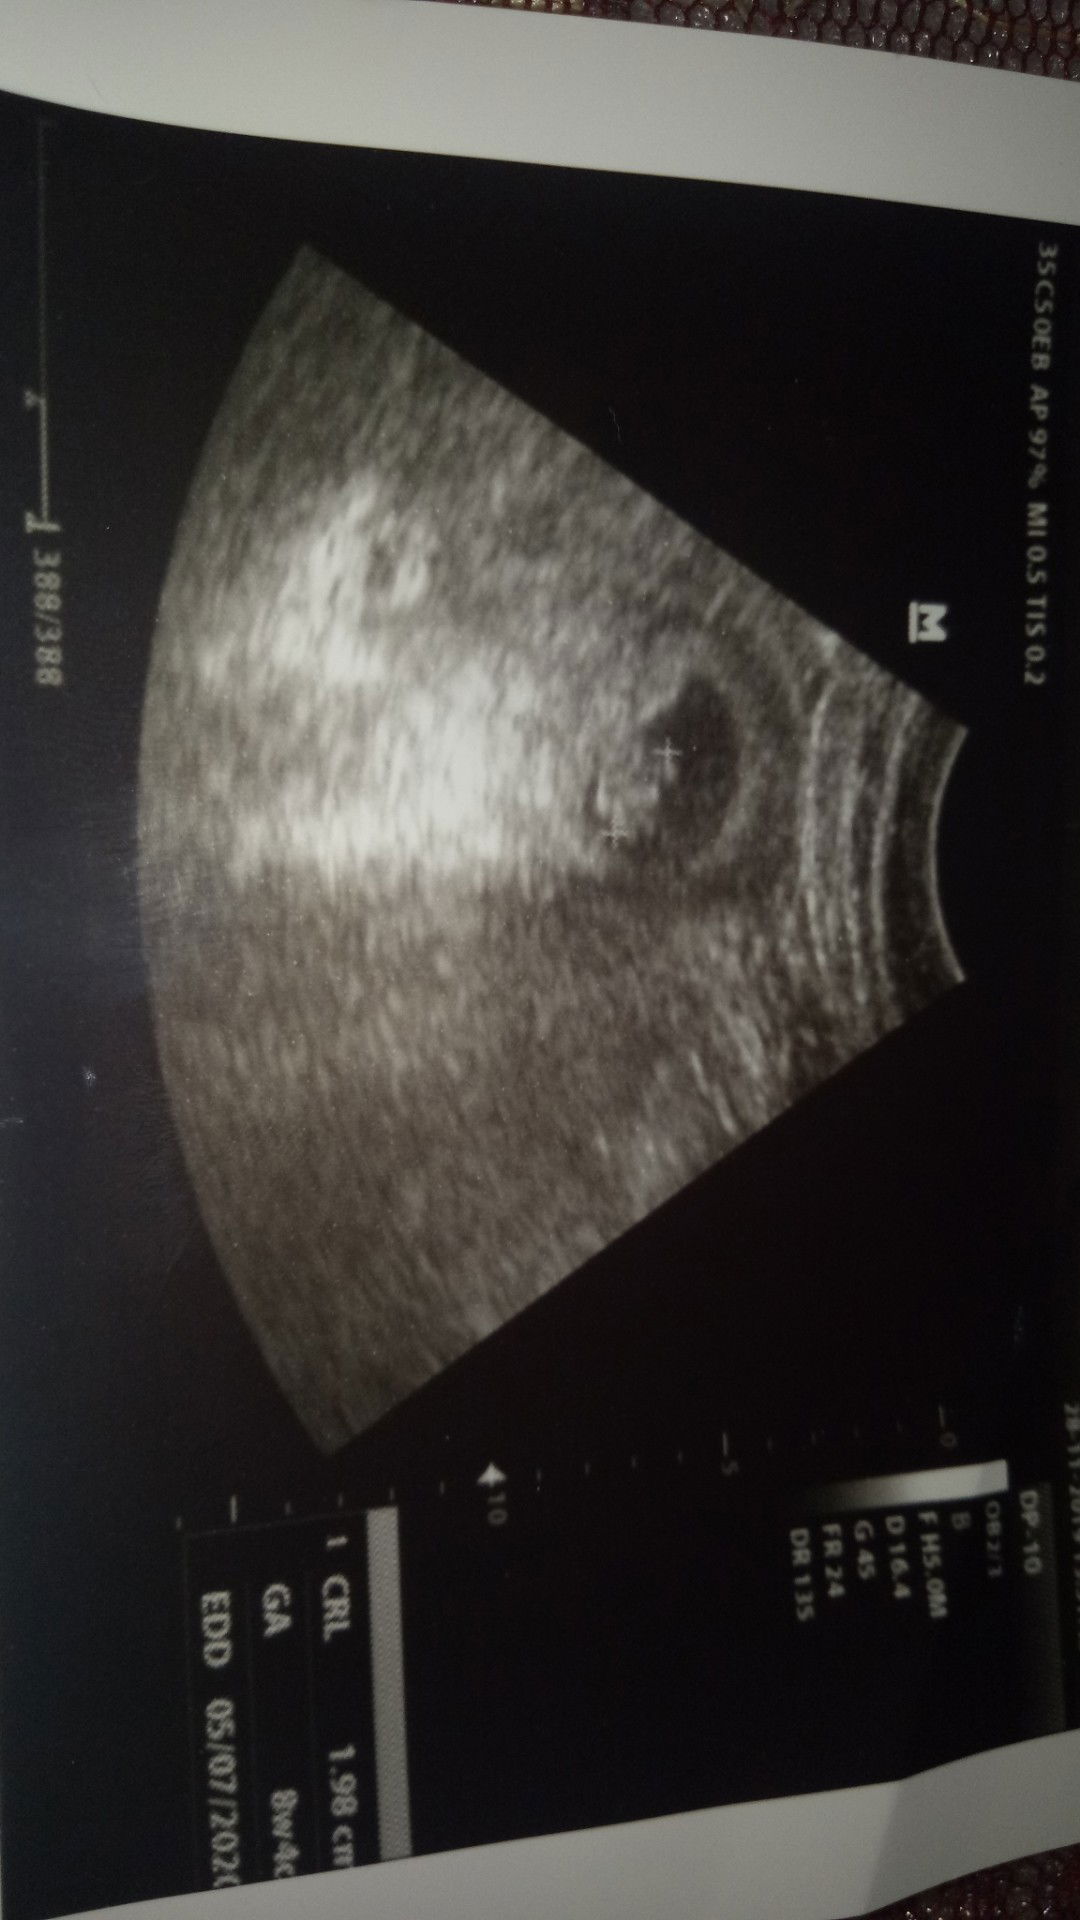

hppl beda 5 hari dgn USG

Alhamdulillah udah terlihat janin nya dan sudah berdetak jantungnua... Semoga sehat selalu smpai waktunya tiba dilahirkan.. Aamiin?